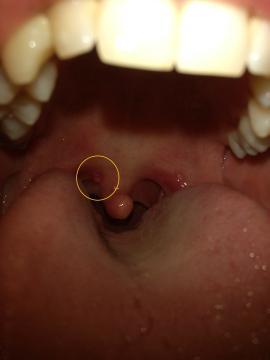

Dobrý den,před nedávnem se mi objevil malý hrbolek v krku a doprovázeli ho mírné bolesti v krku. V tuto dobu bolesti krku už nejsou, ale hrbolek se změnil ve váček (viz foto). Bohužel nemám čas zajít k doktorovi a myslím si že to bude triviální věc. Jen mi váček vadí v krku a nevím jak se ho zbavit. Poradíte mi ? Děkuji Vám za odpověď.

Dobrý den, na fotce jsou patrná i začervenání patrových oblouků, nejspíše vlivem virového zánětu, cystičky u uvuly jsou reakcí na tento zánět, samy postupně zmizí, doporučuji kloktadla (odvar z heřmánku), cucavé bonbóny s antiseptickým účinkem (např. Strepsils).